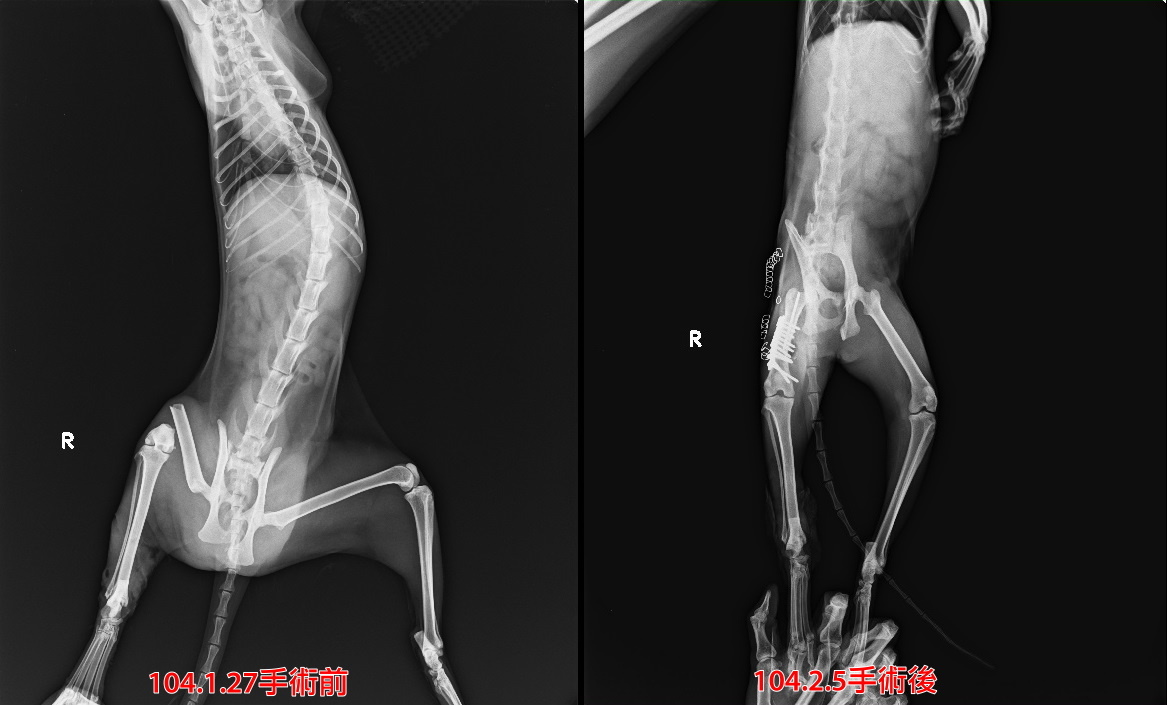

主題: 小宜最後一階段醫療費用 申請者姓名: 臺北市支持流浪貓絕育計劃協會 花色: 申請日期: 2015-08-21 17:58:21 申請者部落格: 申請者臉書網址: 所在縣市/合作醫院: 台北市/沐恩動物醫院 治療費用: 7740元 需求人數: 9人 已結案 (2022-05-13 15:10:47) 報名人員: 大智 x2(已付款)、WeiMin Lin(已付款)、FONG(已付款)、詹曉青(已付款)、ERic YU(已付款)、咪咪 x2(已付款)、Rosalind Tsai(已付款)、 候補人員: 動物病情說明: 小宜

於1月27日領出帶至台北就醫,

前後經過骨折重建術、植皮手術,

所幸貓咪年齡小、復原力極佳,

但因後腿膝蓋無法伸直並會影響到跳躍,

於2015/3/12回到協會安養之家繼續觀察後續復元情況。

六月小宜骨頭部分恢復狀況良好,進行最後一階段手術,將所有骨釘骨螺絲拔除,休養追蹤後,小宜已經不用再回診,完全恢復健康,但是..因為小宜當時沒有足夠的皮膚可以進行縫合,只好移植腹部乳線和部分皮膚,結果...小宜大腿內側乳線...發育良好...有點凸凸的但不影響生活,可想而知小宜是多麼勇敢經歷這麼多的手術,才能恢復健康,希望往後的日子小宜都能一直件件康康,小宜的醫療費用還請各位幫忙。謝謝!